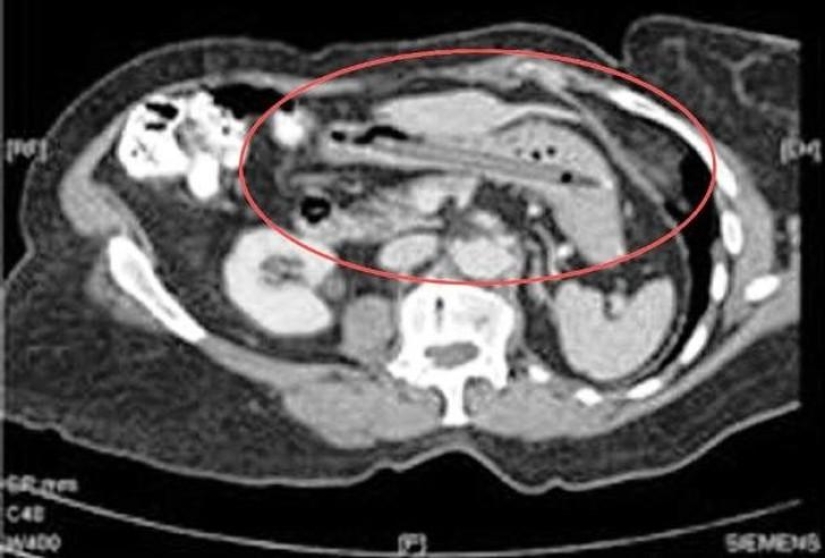

Tijeras.